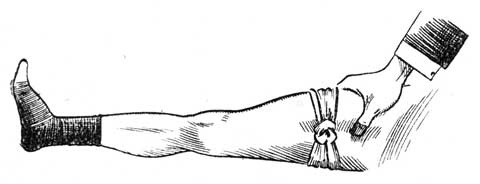

When the bath has done its work, and the limb comes out of the water alarmingly swollen, good and skilful bandaging will do excellent work. If you have at hand an old shirt, or some such thing, tear it into strips about three inches wide, till you have as much material as will swathe the whole limb from behind the toes up to the top of the thigh. This need not be all in one piece, but only so that you may apply it in such a way as to bring a very gentle pressure on the whole surface of the injured limb. It is important that the bandaging should be comfortable. The way in which bandaging is sometimes done is cruel in the extreme. Cases that are a disgrace to humanity are constantly coming under our notice, in which limbs are lost for life by the treatment they receive in this respect. Skilful surgeons do it in the most gentle manner; they even swathe the limbs in soft loose cotton before they apply the bandages, so that a perfectly equal and comforting pressure may be secured. Lay the limb to rest, well and softly supported in a horizontal position. When the swelling falls, gently tighten the bandage from time to time as required. Each time the bandages are removed for this purpose, sponge the limb with warm vinegar or weak acetic acid (see). When the swelling subsides, the ankle may be put again in the hot bath for half-an-hour, and then, if any bones be broken, is the time for setting them right. The ankle will probably turn black. If so, do not apply leeches, but allow the black blood to be absorbed by natural process.